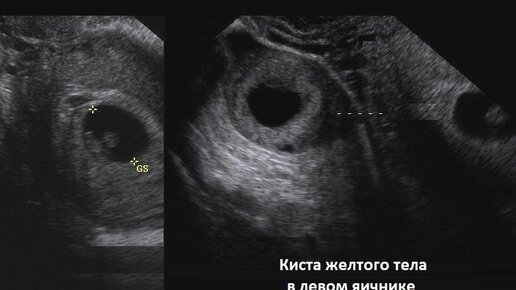

На первом скрининге в заключении УЗИ было написано - анэхогенное образование в левом яичнике. На мой вопрос врачу, что это значит и насколько все серьезно, мне ответили, что так и должно быть (подразумевалось желтое тело). Врачу виднее, хотя интернет выдавал информацию что на 13 неделе уже ничего не должно быть🤨. Второе УЗИ было назначено на сроке 20 недель. В этот раз была другая узист, она считается одной из лучших в городе. Она посмотрела пузожителя, измерила все необходимые параметры и стала смотреть область придатков...